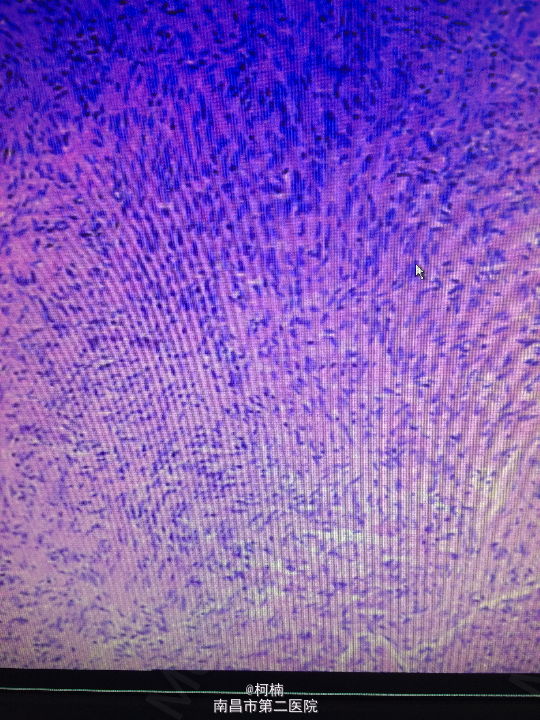

诊断:右侧小脑脑膜瘤 处理:先行介入栓塞肿瘤供血动脉,再行开颅手术治疗,术后予组织病理检查,提示:脑膜瘤